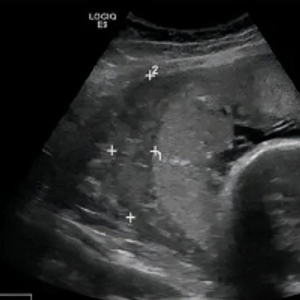

医生经过检查以后,初步诊断为:胎盘早剥。由于情况紧急,在同孕妇及家属充分沟通后,很快进行了剖宫产术,所幸就医及时,加上医生的精准判断及快速处理,现母婴良好。

什么是胎盘早剥:胎盘介于胎儿和母体之间,是维持胎儿生长发育的重要器官。正常妊娠时,胎盘应该附着在子宫体的前壁、后壁或者侧壁。从妊娠20周后正常位置的胎盘在胎儿娩出前,部分或全部从子宫壁剥离,称为胎盘早剥。胎盘早剥是妊娠晚期严重并发症,疾病发展迅猛,若不及时处理可危及母儿生命。

4.定时产检:通过产检,可以更早地发现一些异常情况。倘若发生胎盘早剥,可通过B超及时发现,尽快采取相应对策。